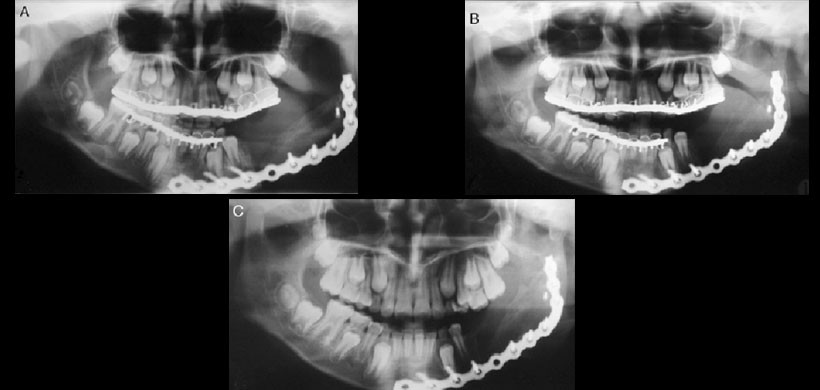

Fig 4.  Controles radiográficos. A) Control de una semana postintervención. B) Control de 3 meses. Nótese la remodelación del segmento condilar del injerto costocondral. C) Control de 6 meses. Se observa una franca remodelación del segmento condilar y una formación de proceso coronoideo.